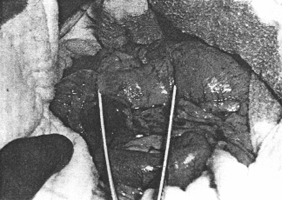

Case 32.2. A.G.C., female aged 64 years. Ten years previously a hiatus hernia had been diagnosed radiographically. At the present examination a large, sliding hiatus hernia with free gastro-oesophageal reflux was demonstrated in the Trendelenburg position (Fig. 32.2A). A constant contraction of the sphincteric cylinder, 5.0 cm in length, was seen (Fig. 32.2B). Its walls were smooth and regular, without evidence of local mucosal destruction, a niche, filling defect or other organic lesion. Emptying of fluid barium suspension was not delayed. At operation there was a hard, tumour-like contraction in the pyloric part of the stomach, extending proximally from the pyloric ring for a distance of 5.0 cm. The contraction was of such severity that the mass appeared avascular and greyish and at first simulated a carcinoma. However, gentle massaging caused it to relax, followed immediately by recurring contraction. A pylorosplasty was done at which the muscularis externa was seen to be three times the normal thickness. The mucosa bulged through the incision and the surgeon had no doubt that it was a case of adult hypertrophic pyloric stenosis (AHPS). There was no other local lesion. The hernia was repaired and a truncal vagotomy performed. Repeat radiological examination 7 months later showed a post-pyloroplasty appearance.

| Fig. 32.2 A,B. Case A.G.C. Large, sliding hiatus hernia (black arrows). Contracted pyloric sphincteric cylinder (white arrows) | |

- The degree of contraction was proportional to the strength of the stimulus. Increasing the stimulus caused increased contraction of the pyloric segment, until it became a solid cylinder. The muscular contraction sqeezed out the blood, the firmly contracted region assuming an anemic, grayish white appearance (Fig. 32.7B). It felt rubbery hard and resembled a neoplasm. Usually there was some contraction of the first and second parts of the duodenum as well, but this commenced a second or two later and was much less marked than the contraction of the pyloric region.

| Fig. 32.7. A Pyloroduodenal junction in the dog. The area in the pyloric region which will undergo contraction is demarcated by the limbs of the forceps (retouched) and is 3.0 cm in length. |

| Fig. 32.7. B Following stimulation of the vagus in the hiatus, the pyloric sphincteric cylinder, demarcated by the forceps, becomes firmly contracted, rubbery hard and anaemic |